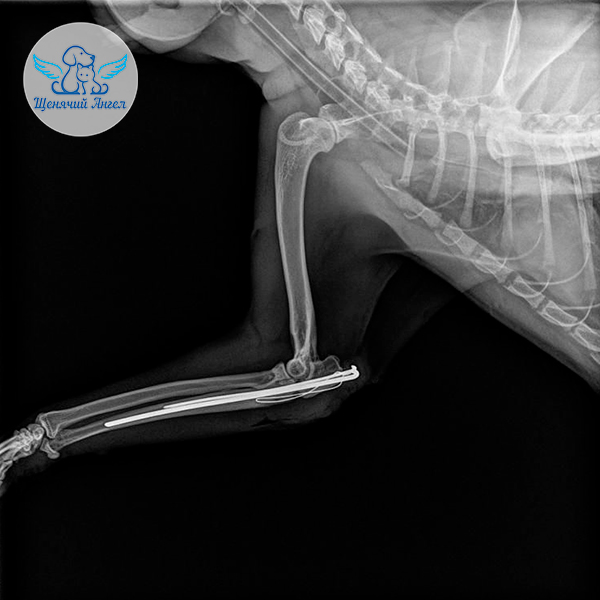

🩻 Рентген выявил перелом правой локтевой кости и пулю! в мягких тканях лапы. Врачи оперативно приняли решение о хирургическом вмешательстве: выполнили остеосинтез, восстановили положение костных отломков и зафиксировали их ❤️‍🩹.

Через три недели Джокер стал сильно хромать, и контрольный снимок показал, что фиксирующая спица сместилась 😔. Такое иногда случается при активных движениях у хвостиков в период восстановления, так как ткани и кости продолжают перестраиваться.

Джокеру провели повторную операцию. Она прошла успешно, и на этот раз костные структуры зафиксировали более надёжным методом ☝🏻.